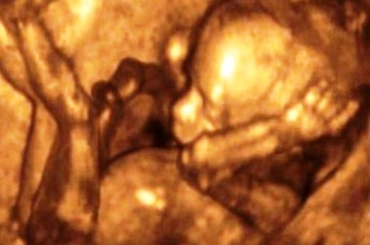

Saptamana 16 de sarcina

Ritmul de crestere al fatului in aceasta saptamana, ultima a lunii a IV-a de sarcina, este incredibil.

Copilul a crescut suficient cat sa-l poti simti foarte bine. Copilul aude, vede, iar simtul mirosului este prezent.